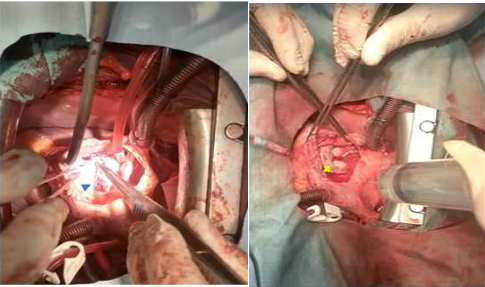

During the intervention: the visual exploration showed a very dilated right chambers, and the tricuspid valve annulus was found to be dilated (enormous), with the rupture of chordae attached to the anterior leaflets; but the valvular tissues were soft without any calcification or vegetation (fig4).

The valve was replaced with 29 bio-prothesis (C-E PERIMOUNT magna mitral ease, model7300 TFX SERIAL 8817944) (fig2); we put a double chambre permanent epicardial stimulation probe as a prevention for conduction abnormalities; the postoperative course was uneventful. Postoperatively, the patient improved significantly. He was discharged on the postoperative 5th day on new oral anticoagulant (thrombix®) and diuretics. During the follow-up, we have noted the worn off the dyspnea with normal heartbeat.

Figure 2: rupture of the chordae of the anterior valve

Bio prothesis ( X)